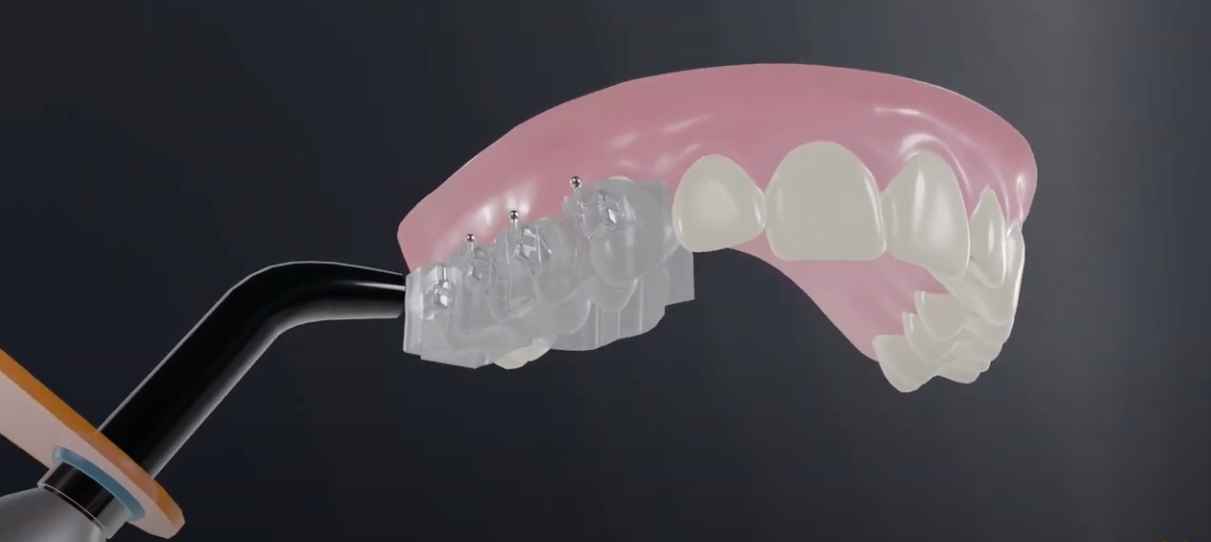

- Biomécanique sur gouttières avec et sans extractions

- Treating Class I Crowding Cases Treatment Planning

- Treating Class II Crowding Cases

- Treating Class III Crowding Cases

- Treating Extraction Cases

- Treating Deep Bite Cases

- Treating Anterior Open Bite Cases

- Orthodontic Elastics and Their Uses

- Orthodontic Expanders and Functional Appliances

- Using Mini-Implants and TADs for Anchorage in aligners